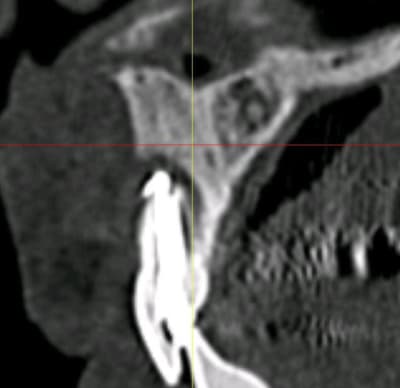

bon, c'est le cas clinique d'un pote (sera peut être plus ensuite, qui sais...) qui c'est décidé de venir me voir suite à un problème sensé être réglé par son praticien habituel au niveau de sa 12 (et 11)

j'attends les images scan pour voir l'ampleur de problème, mais c'est pas jojo...

c'est fistualisé donc c'est plus douloureux...n'empêche qu'il va y avoir du sport amha...

je pense que dans un premier temps, il va falloir aller nettoyer tout çà (et virer le cône de gutta qui dépasse) donc voie chir, obturation à rétro des 2 dents dans la séance

donc: intervention de la "dernière chance" si les images 3D sont pas trop cata...

au minimum: aller cureter tout çà + chir à rétro avec pourquoi pas comblement/membrane

je viens d'avoir les images...

autant sur la 11 çà paraît jouable...autant sur la 12 je pense que c'est mort!!!

faux canal, il ne reste quasi plus rien de la partie vestibulaire de la dent...

point positif: il semblerait que j'ai encore de quoi ancrer une vis sous les fosses nasales en apical de cette 12...

donc amha çà sent l'EII avec mise en vitrine immédiate...et si c'est le cas, je ne ferai pas de quartier à la 11...elle passera elle aussi à la trappe vu le risque de récidive et/ou de contamination du biomat qu'il me faudra mettre pour éviter que tout ne s'effondre...